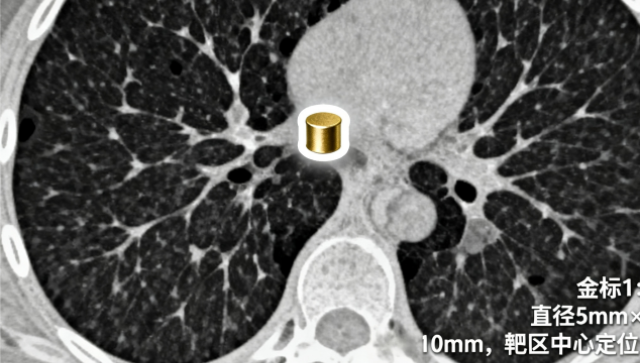

基于高齡及基礎(chǔ)難點患者的肝膽結(jié)石準(zhǔn)確干預(yù)需求,現(xiàn)代臨床采用?“無創(chuàng)分解-代謝調(diào)控-動態(tài)監(jiān)測”的綜合策略?:對于無法耐受手術(shù)的患者(如合并心肺功能障礙或凝血異常),優(yōu)先選擇體外沖擊波碎石(ESWL)?作為非侵入性手段,通過高能聚焦沖擊波將目標(biāo)結(jié)石(直徑≤2 cm且無遠端梗阻)逐步分解為微米級碎片,聯(lián)合口服利膽藥物(如熊去氧膽酸10-15 mg/kg/日)優(yōu)化膽汁流動性,促進碎片經(jīng)膽道自然排出,避免開放手術(shù)對機體的系統(tǒng)性干擾。 適合不同年齡段需求,適用性廣。江蘇智能化結(jié)石臨床解決方案按需定制